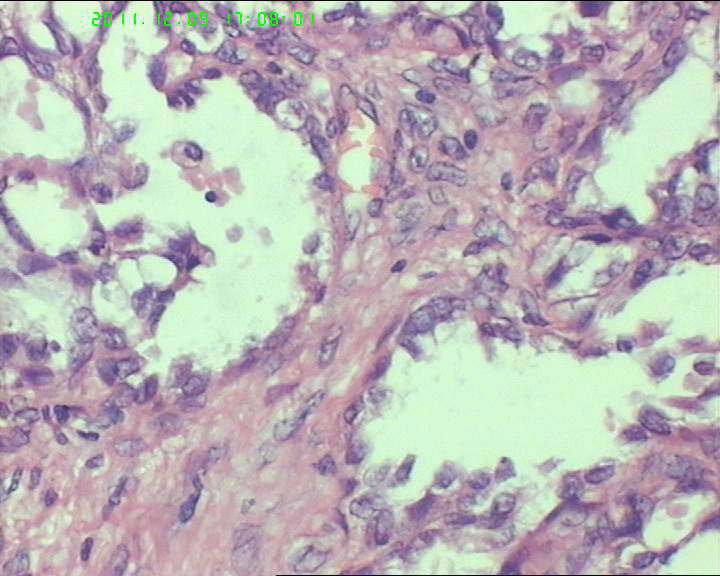

盆腔包块4个月,13*8*7cm 大小,囊实性,实性区菜花状、灰白质脆,局部半透明。

有鞋钉样细胞,首先考虑透明细胞癌。要除外卵黄囊瘤,浆乳癌。

有腺腔样结构,内衬靴钉样细胞,还可见透明细胞,首先考虑透明细胞癌,鉴别诊断:内胚窦瘤。内胚窦瘤的网状结构内衬是扁平的上皮。

肿瘤细胞弥漫性生长,细胞排列成腺样、腺泡状,细胞异型明显。突向腔内。